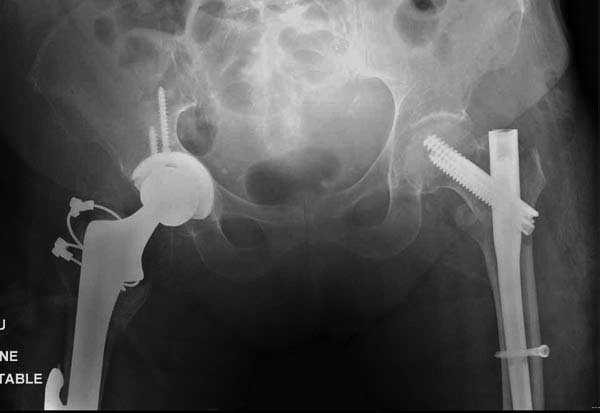

Третья операция-продолжения усилии “синьорами пэрами” по разрушению нормальной анатомии. Крест на головку! По видимому возраст позволяет биполярную конструкции, и при дефекте  calcar пошли на обычный цементный. Ягодичные мышцы потеряли связь с вертелом, т.е. отсутствует верхний удержатель, и результат “a Big Screw Up!” Снимки вызывают головокружение!

Если хирурги не устали от своих “творчеств”, тогда можно ре-оперировать с calcar replacement stem, и собрать остаток ягодичных мышц. Глубина и отстутствие артроза позволяет применить любой, биполярный или тотальный, хотя принять решение можно после ревизии ацетабулума.

Такие “чужие осложнения” встречаются у всех и представляю банальный случай, который шаг за шагом показано как перерос в более сложный процесс... Больная 70 лет, множественные ко-морбидности, чрезвертельный перелом первоначально фиксирован Гамма 3. Осложнение в течение 6 недель, ревизия тотальной артропластикой и во время установки ножки обнаружена трещина диафиза (17), из малого доступа фиксация алло-графтом.

Обычно после чрезвертельных переломов, за исключением молодых, у пожилых остается нестабильность при движении. Часто падают и после 3х мес. в результате падения обнаружен перипротезный перелом (22-23), который зафиксирован Синтез пластиной.